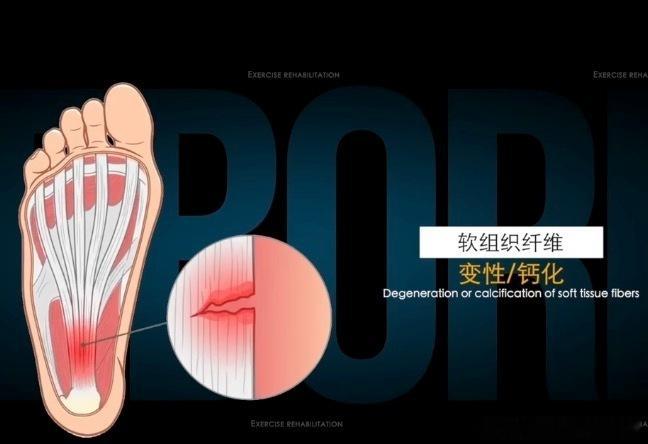

【足底筋膜炎治疗禁忌】⚠️①不要过度刺激——足底筋膜炎其实是微细的软组织撕裂,如果我们再重的手法或剧烈的牵拉,对于重度足底筋膜炎来说,可能会产生二次损伤。

②不要打封闭——打封闭对于足底筋膜炎,短期有立竿见影的缓解,但是封闭中的糖皮质激素可能让软组织变脆变性,反而容易进一步产生撕裂。